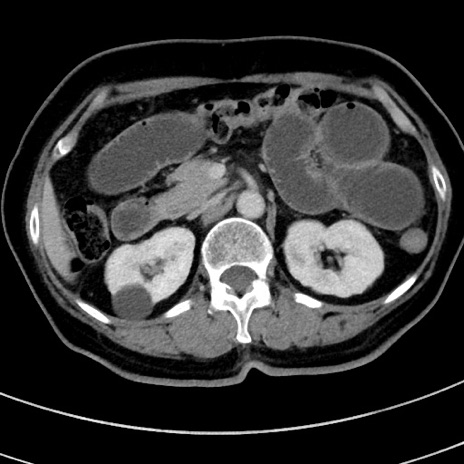

症例9(横断像)

【症例】 60歳代女性

【主訴】むかつき、みぞおちの痛み

【現病歴】3日前よりむかつきがあり、食事がとれない。

【既往歴】糖尿病

【身体所見】発熱なし、心窩部圧痛軽度あるも、腹膜刺激症状なし。

【データ】WBC 7400、CRP 1.92